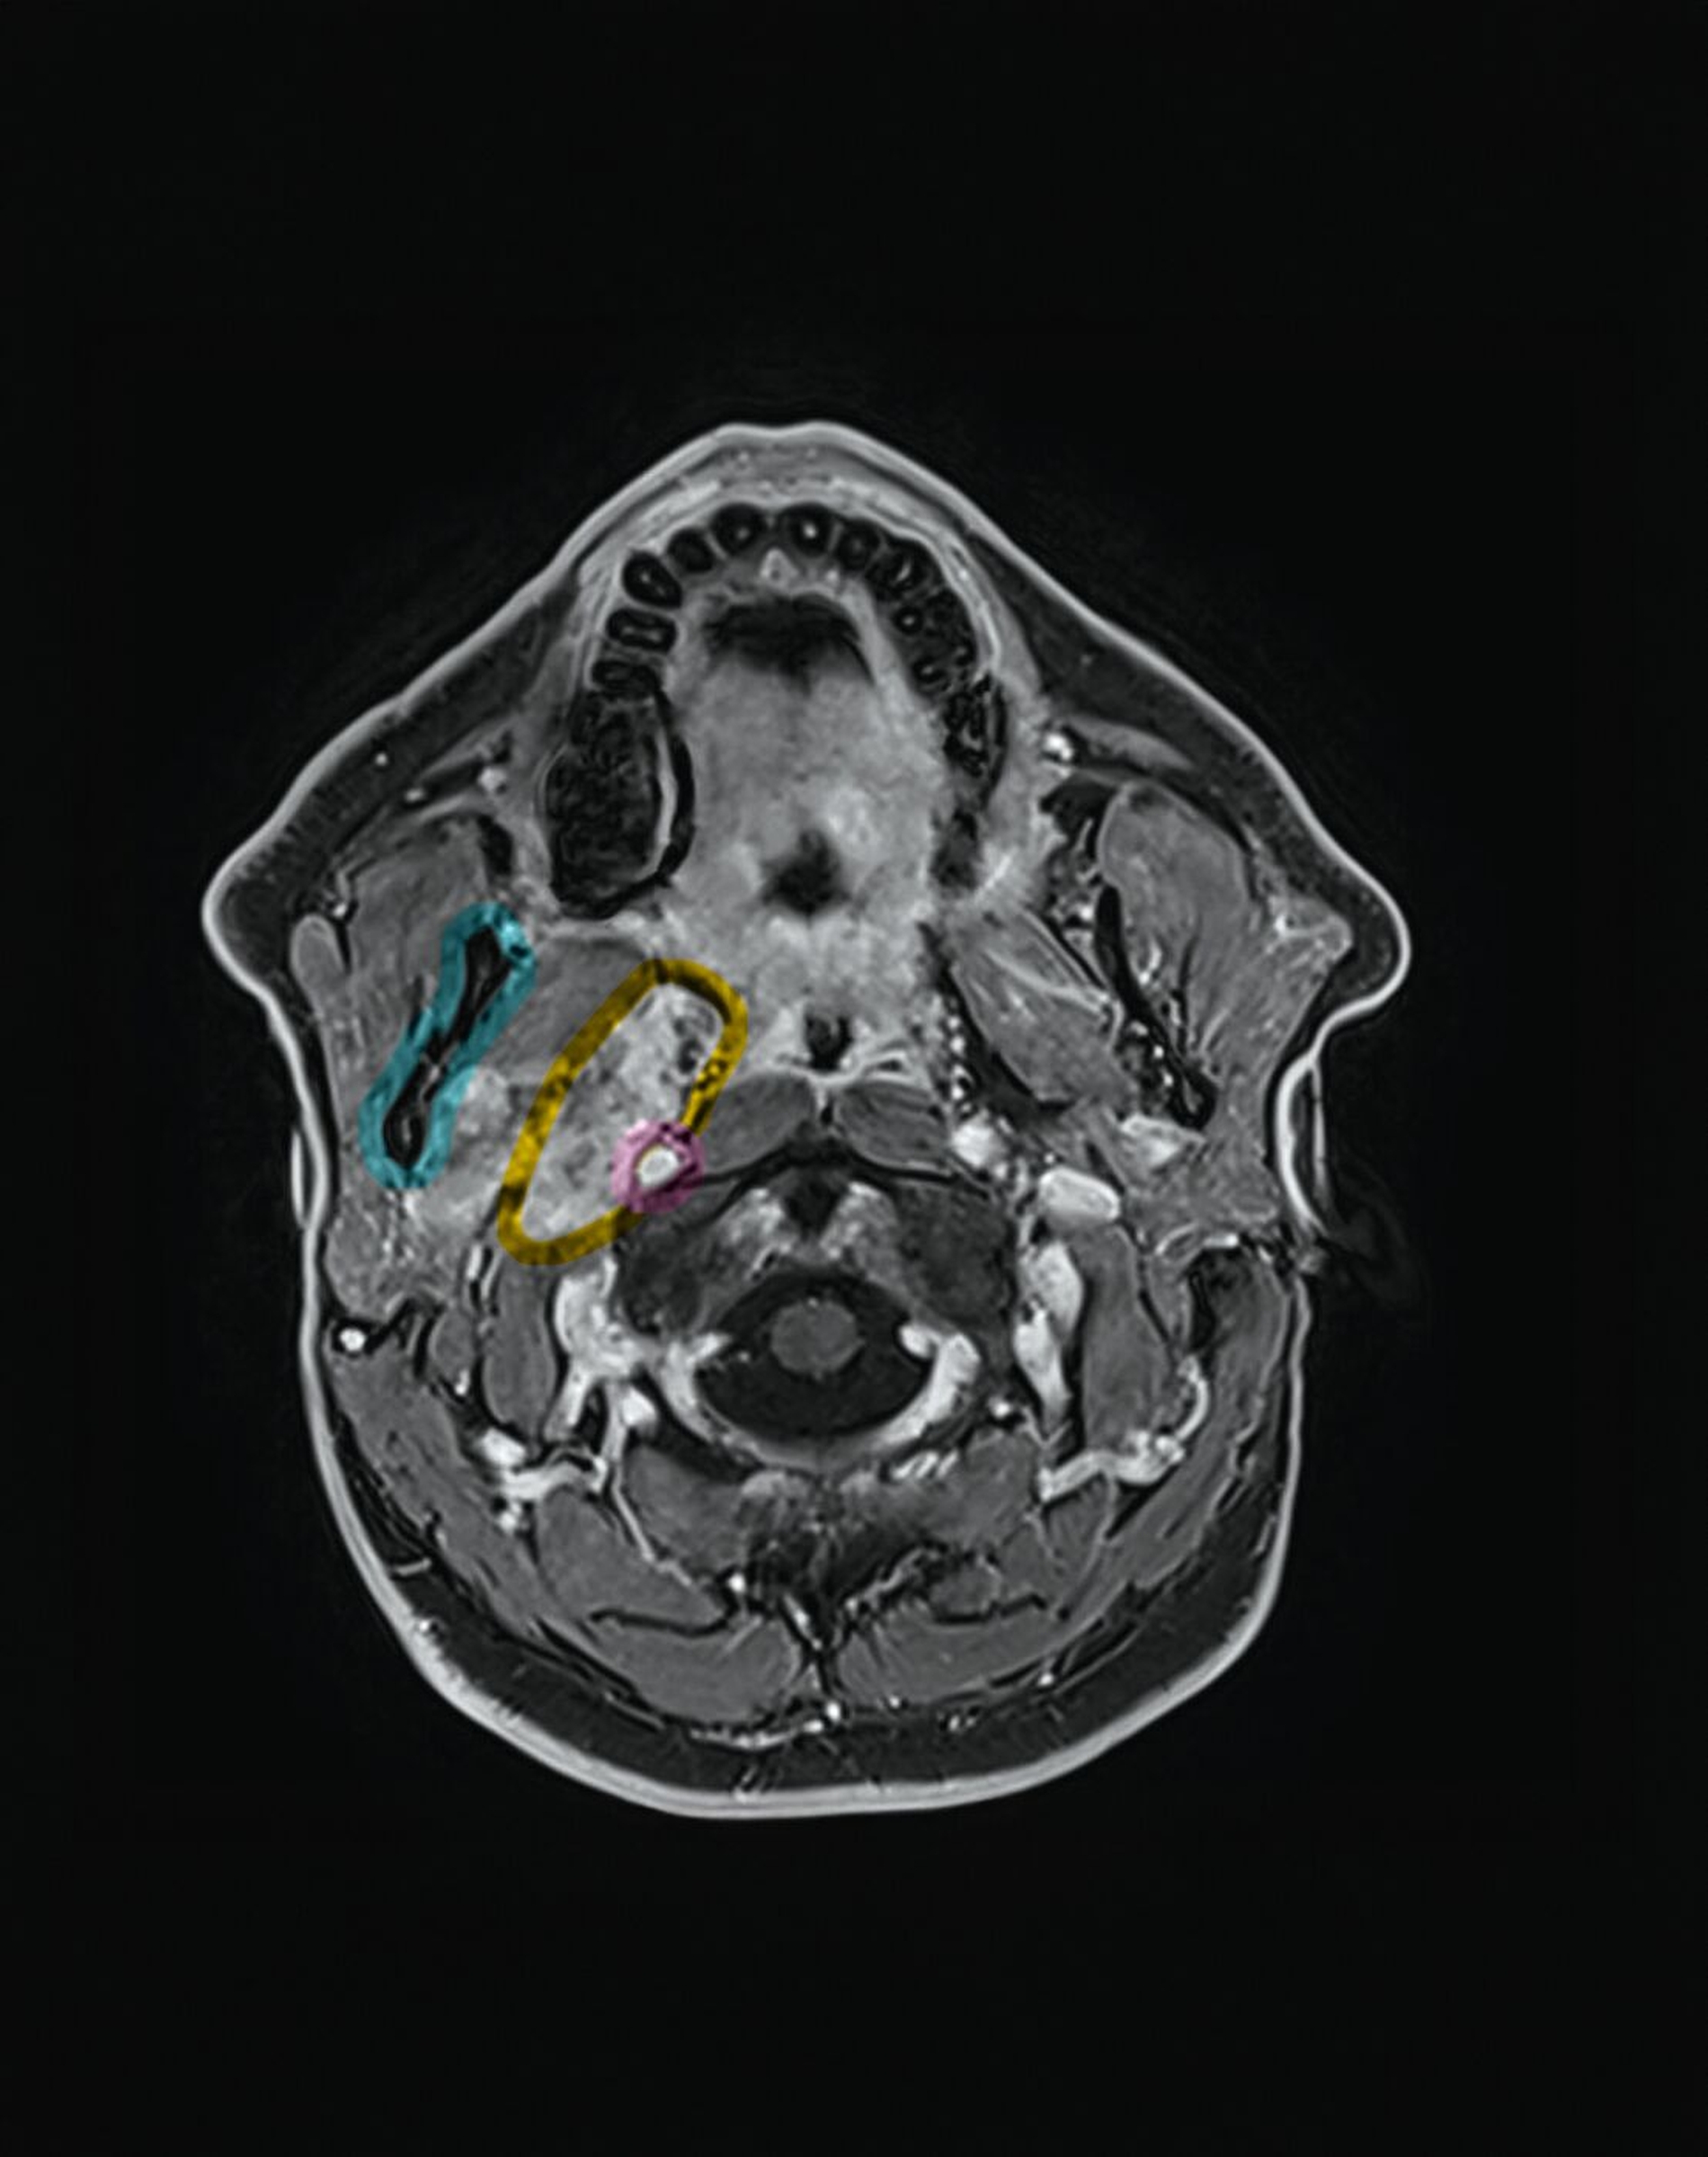

Zur besseren räumlichen Einschätzung wurde das MRT-Datenset mittels der Open-Source-Software 3D Slicer segmentiert [Fedorov et al., 2012]. Mithilfe der Funktion „Grow from seeds“ erfolgte eine separate Segmentierung des Unterkiefers und der Raumforderung, ergänzt durch manuelle Korrekturen.

Metallartefakte durch zahnärztliche Restaurationen im rechten Unterkiefer wurden berücksichtigt. Die dreidimensionale Rekonstruktion verdeutlichte die enge Beziehung des Tumors zur A. carotis interna und unterstützte die Indikationsstellung für einen erweiterten operativen Zugang.